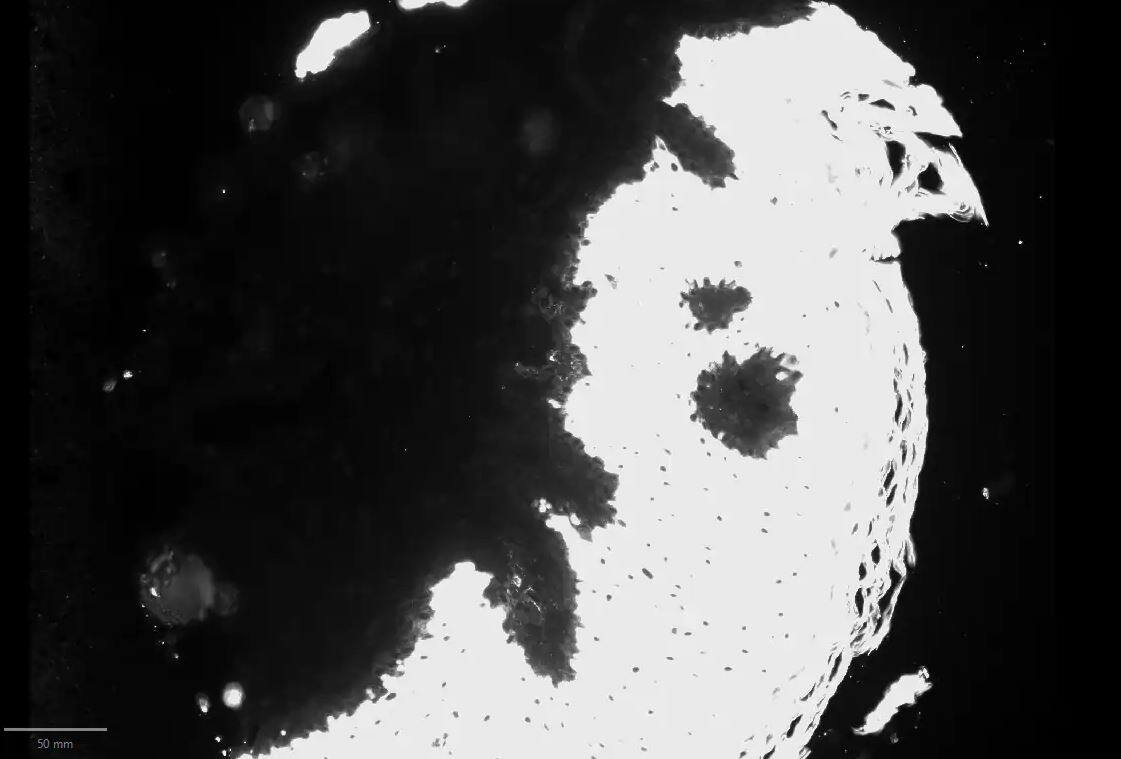

Immunohistochemistry-Paraffin: Cytokeratin 10 Antibody (SPM623) [NBP2-54332] - Formalin-fixed, paraffin-embedded human Bladder Carcinoma stained with Cytokeratin 10 Monoclonal Antibody (SPM623).

Immunohistochemistry-Paraffin: Cytokeratin 10 Antibody (SPM623) [NBP2-54332] -

Immunohistochemistry-Paraffin: Cytokeratin 10 Antibody (SPM623) [NBP2-54332] - CK10-positive human FFPE skin tissue section. Image from verified customer review.